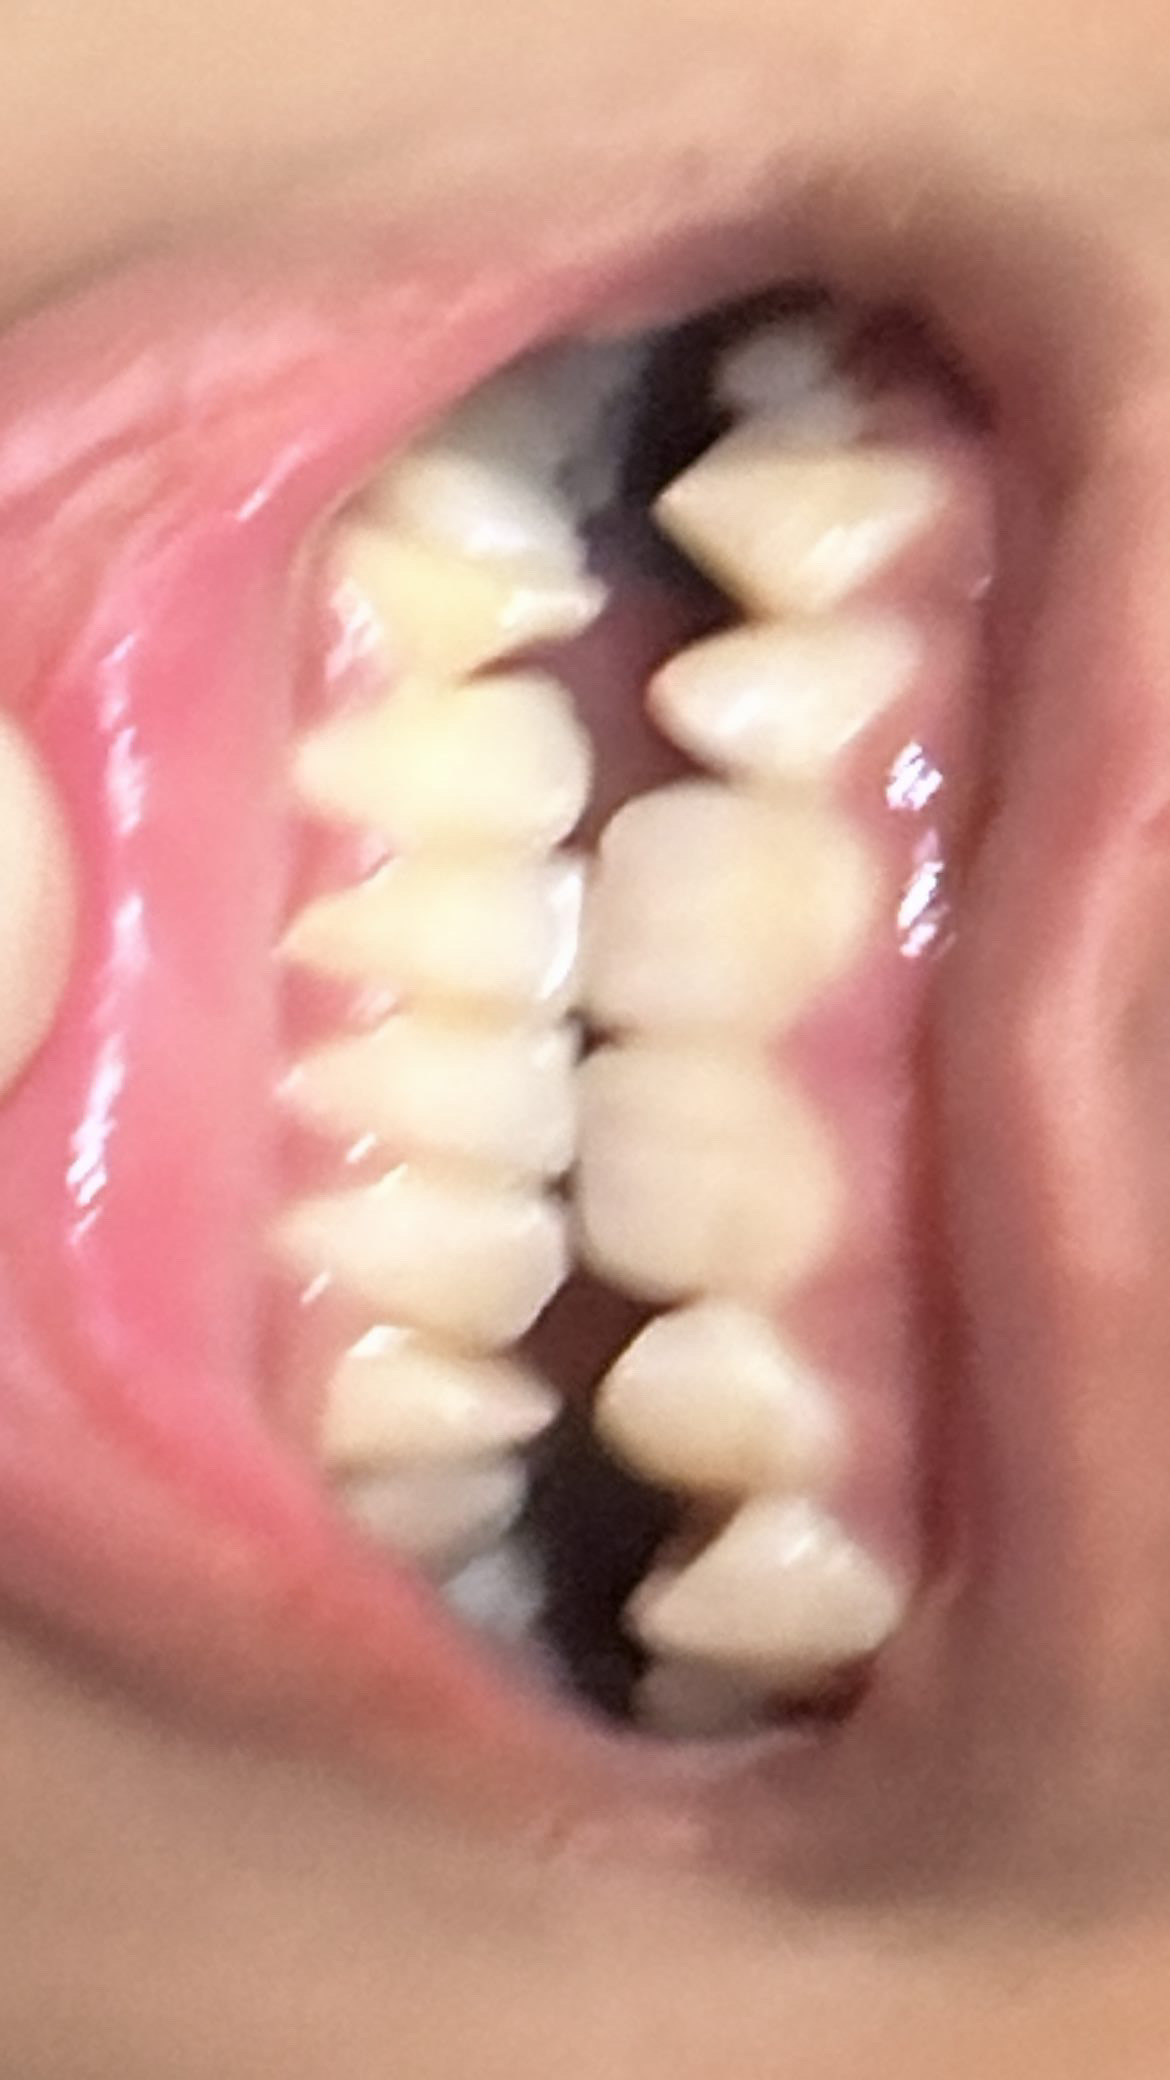

My primary incisors are prominent but they bulge inwards my secondary incisors are really sideways and my canines are decent but maybe can be straighter

But my first incisors need to be pushed outwards and secondary incisors need to face straight instead of side

Your palate is near death teir get palate expander for upper and lower jaw

you can’t push your teeth out, you’d need to move the bone to push your teeth out forward or just bend ur teeth 45* which is retarded and no one would do that for you